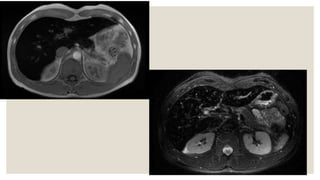

Hemosiderosis

Turtle back appearance

Schistosomiasis.

characteristic pericapsular and periportal calcifications, which give the liver a

tortoise shell appearance.

The calcifications form as a result of embolization of the schistosome eggs to

these areas in the liver, with ensuing inflammatory reaction and fibrosis.